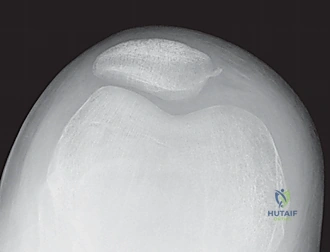

* Nonarticular Avulsion Fracture: A less serious avulsion fracture of the MPFL off the medial patella is pathognomonic. This can appear immediately or be delayed as an ossific lesion.

- AP, Lateral, Sunrise/Merchant Views: Essential. The sunrise view, requiring 30-45 degrees of flexion, might be delayed due to acute pain but is crucial for assessing trochlear morphology and patellar tilt.

- Limitations: Plain films can miss up to 40% of arthroscopically documented chondral or osteochondral lesions. Subtle slivers of bone can be easily overlooked.